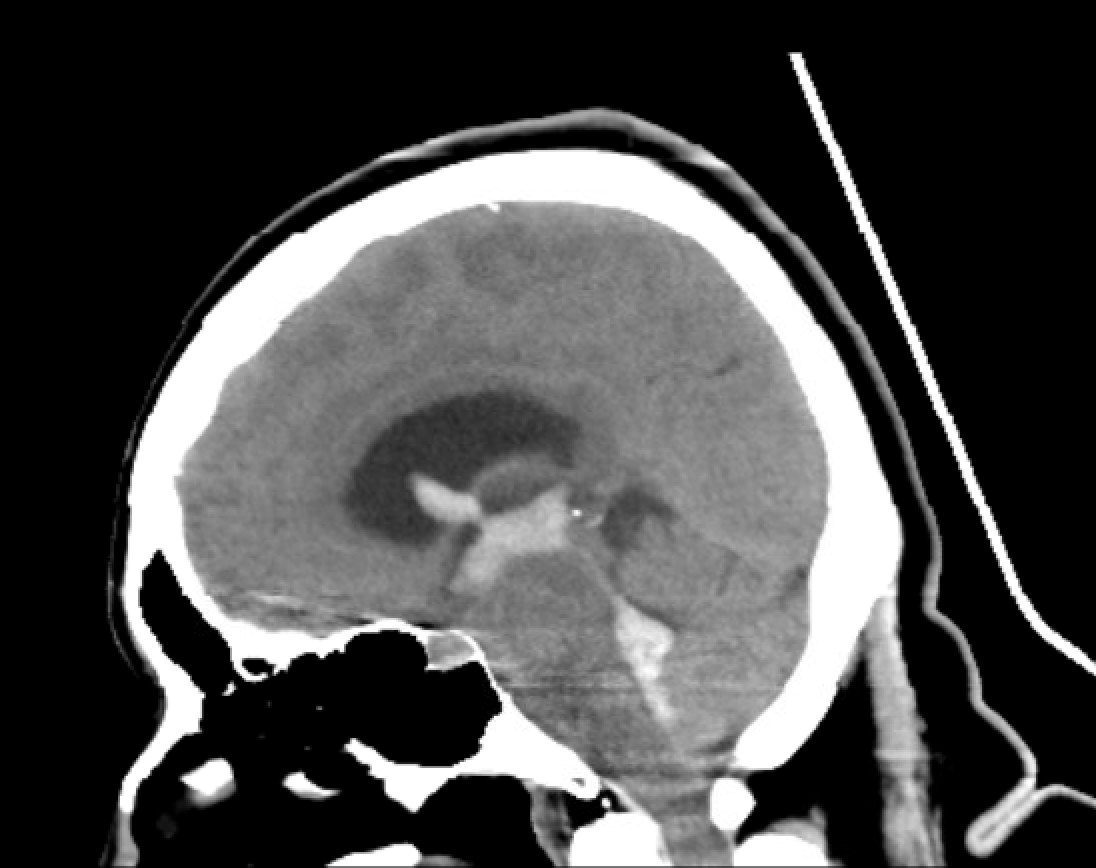

Noncontrast CT Head, Sagittal View: See extensive hyperdensities that extend from the 4th ventricle, through the 3rd ventricle, to the lateral ventricles.